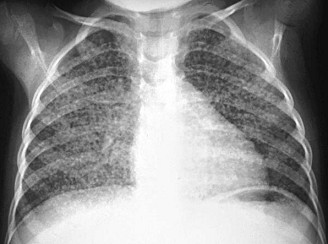

TB lung with tubercles, X-ray photo [1]

Persons with tuberculosis (TB) are suffering a chronic undernourishment and are suffering a weak immune system. Symptoms of tuberculosis are add to this <fatigue and weakness, missing appetite and loosing of weight, swollen lymph nodes, some fever above all in the afternoon, sweat in the night and a constant not stopping slight cough without much sputum.> [web01]